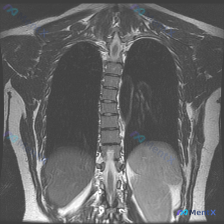

整理到一份临床诉求指向「脊柱侧弯」的病例资料: 仅有的影像检查是胸部MRI冠状位T2加权像,影像报告的核心发现是: - 双侧肺野、纵隔、心影未见明显局灶性病变或占位; - 胸椎序列清晰,椎体形态基本正常,未见明显的形态异常或骨质信号改变; - 双侧胸廓、软组织结构大致对称。 但结合「脊柱侧弯」的核心...

整理了一份影像分析资料,觉得这个矛盾点挺有意思的,拿出来和大家讨论。 资料背景是:一张胸部MRI T2加权像(冠状位),临床核心诉求是排查脊柱侧弯。 先放几个关键的影像所见: - 肺实质、纵隔、胸膜腔、胸壁软组织都未见明显异常信号或占位 - 报告写了“胸椎椎体及附件形态基本完整”、“脊柱旁软组织未见...